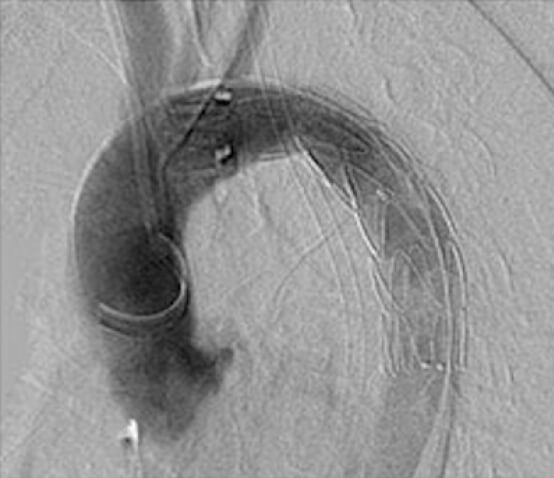

下肢閉塞性動脈硬化症による足の壊死(最近の専門用語では、包括的高度慢性下肢虚血、CLTIとも呼ばれます)は進行性で治療が大変に難しい病気です。この病気は全身の動脈硬化の末期像と考えられており、心臓病や脳梗塞などで体力が落ちている患者さんに、長期の治療が必要となるため、治療方針の決定には高度に専門的な判断を必要とします。埼玉医科大学総合医療センター血管外科では、これまで評価が難しかった足の微小循環を、最新の核医学検査を用いることにより評価する研究を行っています(Hashimoto et al. Eur J Vasc Endovasc Surg 2025, Hashimoto et al. EJVES Vascular Forum 2025)。これらの知見は、血流を改善する手術やカテーテルの継続によって足を残す努力を続けるか、足を早期に切断することによって体力を温存するか、患者さんが迫られる難しい決断の助けとなり、生活の質の向上に寄与する可能性があります。

1. 99mTc-tetrofosminを投与し撮像したRNアンギオグラフィの累積画像。

右下肢のCLTIに対するバイパス手術後。

2. 右足部断端は植皮により遅滞なく治癒した。

3. 左足部は1年後にCLTIを呈した。